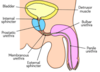

How long is the urethra and where is the membranous part?

- F: 4cm

- M: 20cm

As it passes through urogenital diaphragm